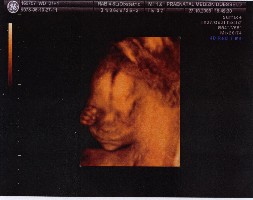

Und wenn wir es dann wissen ,sagte er zu mir ,dann verraten wir es keinem und meiner Mutter werde ich dann immer sagen ,ich weiß was ..........nanananana! Ich bin mir da noch nicht so sicher ob ich es wissen will.Na wir werden sehen was kommt.Der US war so schön und mir kommt es vor ,als wäre es schon ewig her und jetzt müssen wir ganze 4 Wochen warten bis zum nächsten.Dabei sind gerade erst 2 Tage vergangen. Aber ich wir haben die 12 Wochen schon mal geschafft .Bin jetzt in der 14 Woche,neeeeeeee sorry ab heute ist es ja die 15 SSW

Doro meine Liebe,bald hältst du dein Glück in deinen Armen.Das ist echt klasse!!!!!! was du zur Renate gesagt hast ,da kann ich dir nur voll und ganz zustimmen. Dieser 3D Ultraschall,dass nennt man doch auch Organscreening,oder?Wollte das aufjeden Fall machen lassen,wird uns zwar sicher wieder was kosten,aber schitt drauf,finde das sehr sinnvoll.Obwohl mein Mann mittlerweile auf den Standpunkt steht,was soll das alles ,ist doch alles nur wieder zum bekloppt und Sorgen machen.Er würde am Liebsten in dieser Richtung nichts mehr machen.Denke es liegt daran,dass wir ja echt ziemlich lange jetzt auf das Ergebnis warten mußten und da macht man sich natürlich verrückt.Werde ihn aber schon überzeugen.In dem Bericht steht auch,dass sie eine Untersuchung empfehlen in ab der 15 /16 Woche auf z.B offenen Rücken und noch was ,weiß nicht mehr genau.So wie ich es verstanden habe,wird das auch durch Blutabnahme dann bestimmt. Mein Doc erwähnte das nicht......hmmmm

Hast du oder auch Anett das machen lassen? Werde ihn jedenfalls mal ansprechen.Kann man das dann auch 18/19 Woche rum noch machen,weiß das Einer von Euch?Da ist mein Männe im Moment auch gegen. Aber diese 3 Dinge fand ich bisher für mich wichtig,1. NFM,2. offener Rücken per Blutabnahme,glaube ich und 3. das Organscreening 3D oder auch Feinultraschall genannt,glaube ich .

Gerade 3D ,das hört sich so gut an und ich denke ,wie du schon sagst Doro,dass wir das nicht verpassen sollten.